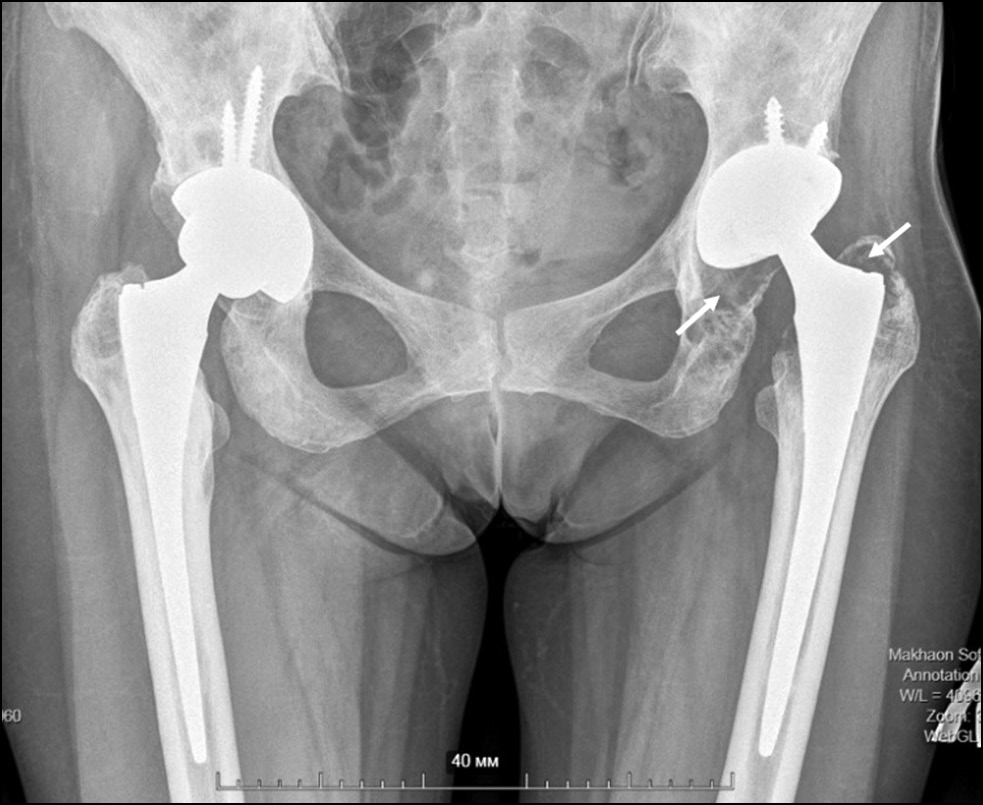

Закономерно, что эндопротезы, имеющие пару трения с улучшенными трибологическими характеристиками, такую как К/К, К/ПЭ и МодМе/ПЭ, показали большую долговечность в сравнении с парой трения CoCr/ПЭ. Полученные результаты согласуются с данными исследования D. Cohen, проведённого на большой когорте пациентов с БГ [14]. Продукты износа ПЭ на фоне повышенной активности тканевых макрофагов при БГ могут приводить к образованию обширных остеолитических гранулём, усложняющих ревизионные операции (рис. 8).

Рис. 8. Остеолитическая гранулёма (указана стрелками) у пациентки с болезнью Гоше. 10 лет после первичного тотального эндопротезирования тазобедренного сустава. Пара трения — кобальт-хромовый сплав по полиэтилену.

Fig. 8. Osteolytic granuloma (indicated by arrows) in a patient with Gaucher disease 10 years after primary total hip arthroplasty. Friction pair — cobalt-chromium alloy on polyethylene.